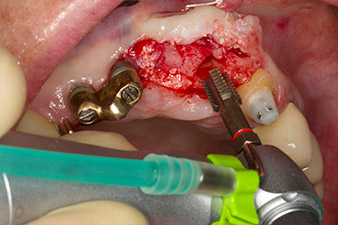

Nach primärer Abheilung werden die Weichgewebe mithilfe der basal unterfütterten Brücke ausgeformt. Zwei Monate später erfolgt die Freilegung mit einem leicht palatinal gelegten Kieferkammschnitt (Abb. 2).

Der Alveolarknochen erweist sich an Position 22 als ausreichend dimensioniert. Die Abbildungen 2 und 4 zeigen die Implantatbett-Aufbereitung, den Gewindeschnitt und die Implantation mit dem Implantmed.